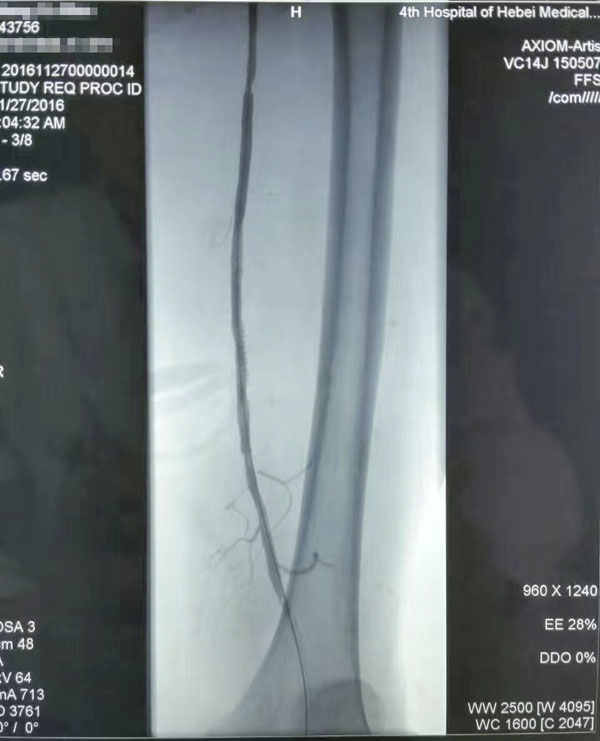

介入治疗前后对比

糖尿病足重在预防,而预防和治疗下肢血管病变是防治糖尿病足的有效措施。下肢血运重建是糖尿病下肢血管病变治疗的根本采用球囊扩张开通狭窄或闭塞的下肢动脉(介入治疗),恢复直达足部的血流,是治疗糖尿病下肢血管病变的根本措施,具有立竿见影的效果这也是近年来在糖尿病足诊治方面取得的又一新进展,为广大糖尿病下肢血管病变患者解除了痛苦使糖尿病足患者截肢率由34%降至4%。世界防治糖尿病日到来之际,希望广大糖尿病患者关注糖尿病下肢血管病变,保护自己的双足,做到早发现、早治疗,提升幸福感快乐每一天。